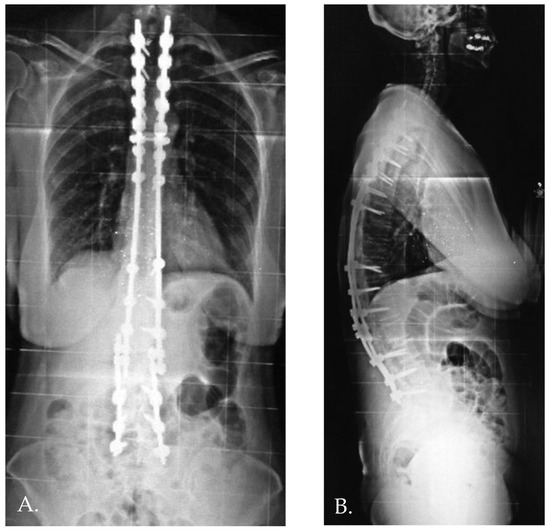

Distal junctional kyphosis (DJK) occurred in two patients, both in Group 1, where the fusion area included only the first lordotic vertebra. One patient, a 24-year-old female, was asymptomatic and maintained satisfactory correction at the 3-year follow-up. The second patient, a 23-year-old female, developed significant symptoms at the 3-year follow-up, including distal implant failure (Figure 2), which worsened her clinical condition. She experienced intractable back pain and significant sagittal and coronal imbalance. Due to hardware failure and clinical deterioration, revision surgery was required. The revision included extending the fusion to L5, interbody fusion between L1 and L2, and multiple Smith–Petersen osteotomies (Figure 3). At the 6-month follow-up, the patient showed good balance and a satisfactory reduction in pain.

Figure 3. Anteroposterior and standing lateral radiographs (A,B) after revision surgery.